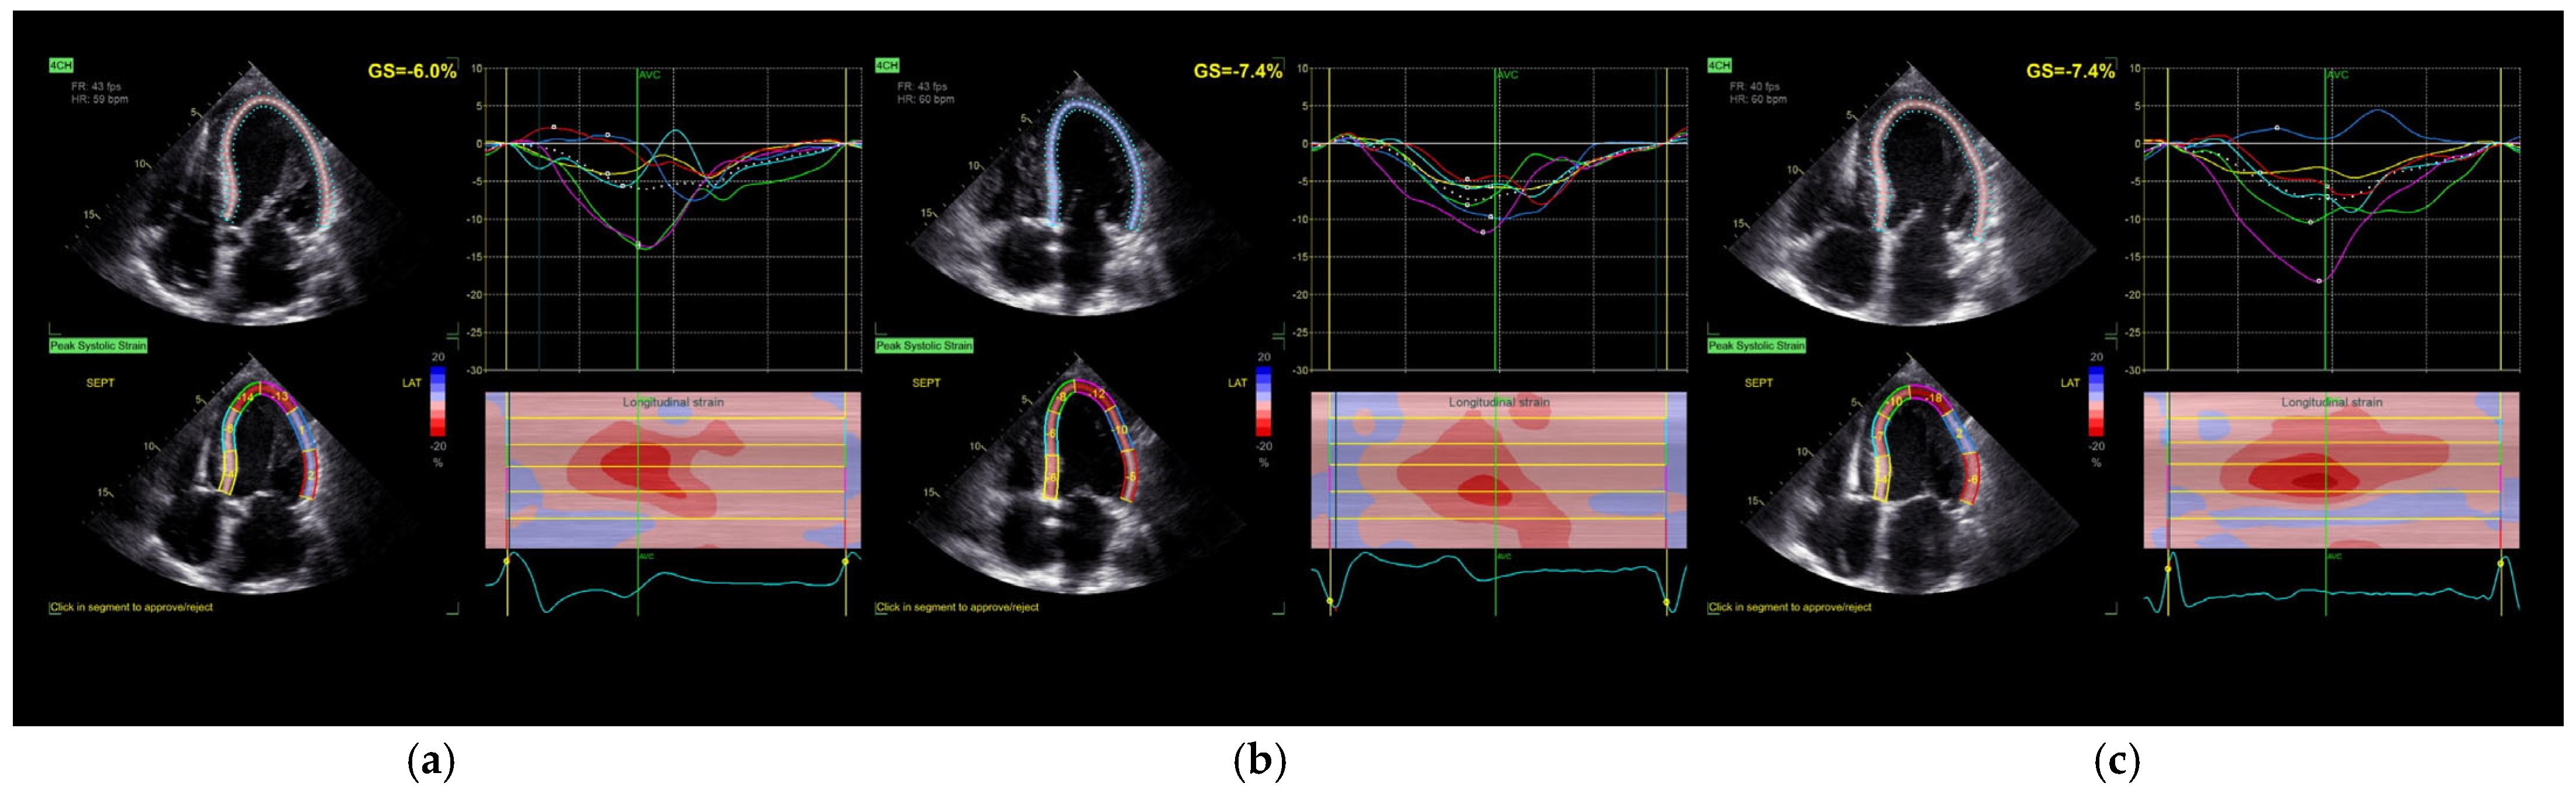

Figure 1. Longitudinal strain assessment in the four-chamber view: (a) without stimulation; (b) BiV stimulation; (c) SyncAV stimulation. GS—global longitudinal strain; AVC—aortic valve closure.

Global longitudinal strain (GLS) of the left ventricle did not show statistically significant changes in response to either pacing strategy (p = 0.212), although a mild trend toward improvement was noted following biventricular pacing. Importantly, the time to peak longitudinal strain (Peak SL) was significantly reduced under both pacing modes compared to baseline (p = 0.015), reflecting improved mechanical synchrony. Additionally, SyncAV® pacing was associated with a prolongation of aortic valve closure time, suggesting enhanced contractile force [17].

4.4. Mechanical Synchrony and Segmental Strain

We observed significant improvements in segmental synchrony metrics such as Peak SL and aortic valve closure time (AVC), particularly with SyncAV. These findings suggest that fusion pacing can influence contraction timing favorably even when global metrics remain stable. This observation is supported by the acute findings of Tam et al., who demonstrated that real-time ECGi-guided CRT, based on activation time reduction, correlates strongly with later echocardiographic improvements, even in non-LBBB patients [22]. However, we acknowledge that while statistically significant, the changes in Peak SL and AVC have not been validated against minimal clinically important difference (MCID) thresholds in CRT populations. Future studies incorporating anchor-based clinical metrics are needed to contextualize these findings.